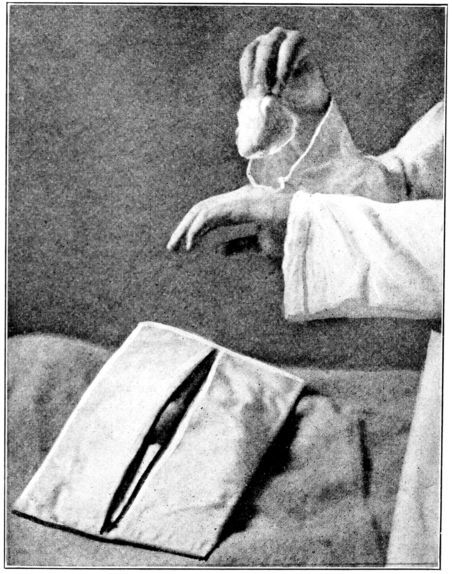

| 77. | Powdering hands before putting on dry gloves | 254 |

| 78. | Successive steps in proper method of putting on gloves | 255 |